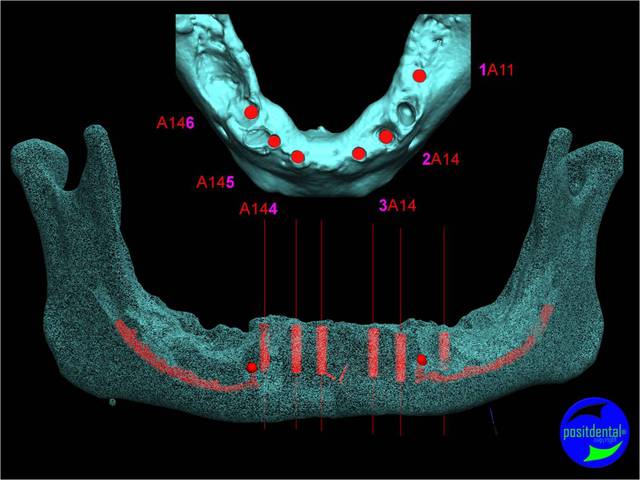

Extraction, pose d’implants Ankylos, pose des piliers Standard définitifs, mise en charge immédiate bi-maxillaire en une chirurgie.

Maxillaire supérieur – extraction 13, 26, 7 implants en MCI, 1 implant en MCR pose summeurs, densification par ostéotme, comblement osseux, bridge provisoire sans fausse gencive avec renfort métallique.

Maxillaire inferieur – extraction 35, 34, 44, 45, 6 implants MCI, comblement osseux, bridge provisoire sans fausse gencive avec renfort métallique.

en attendant la pano voici les coupes de la S.I.A.O.